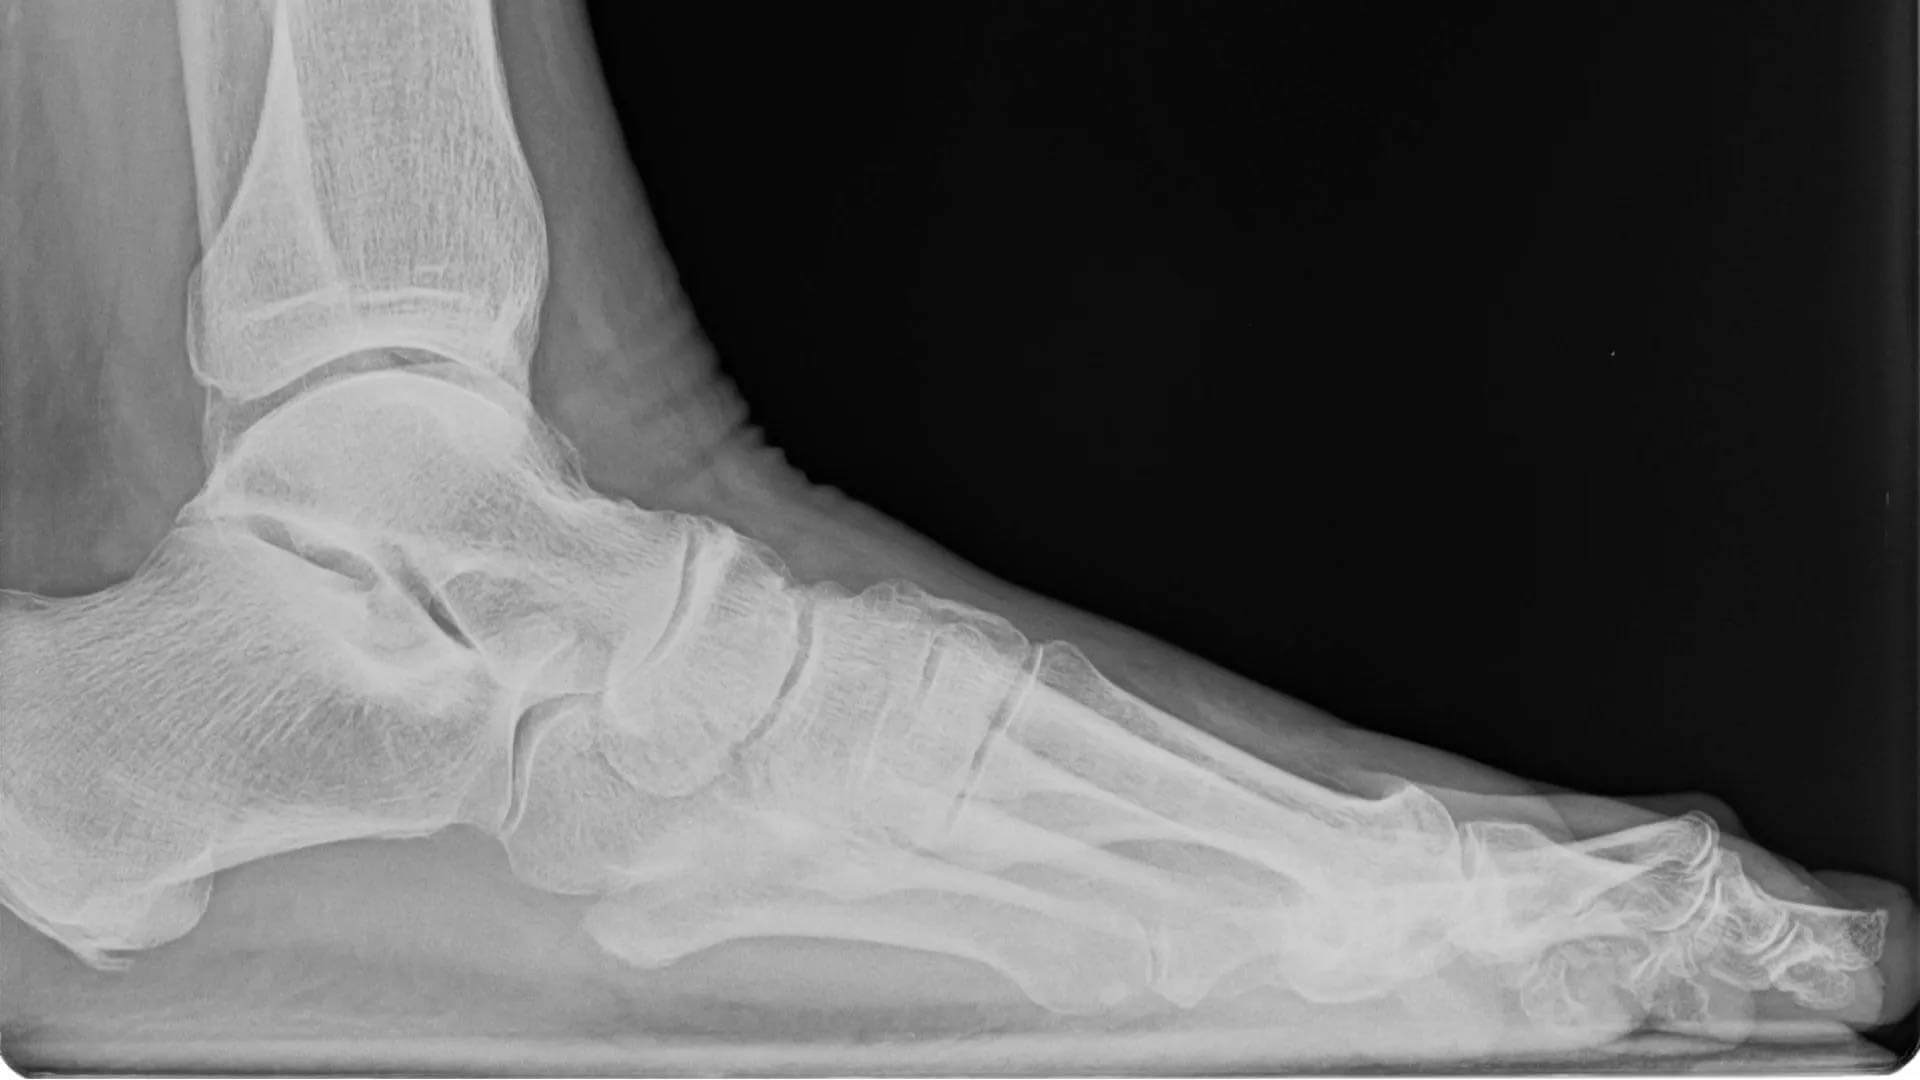

My contracted toe, or hammer toe. r/XRayPorn Hammer Toe Definition a hammer toe is a toe that curls down instead of pointing straight forward, which can make walking uncomfortable. hammertoes happen when something puts pressure on your toes and pushes them out of place. hammer toe is a condition that causes the middle joint of the second, third, or fourth toe to bend down and resemble a.. Hammer Toe Definition.